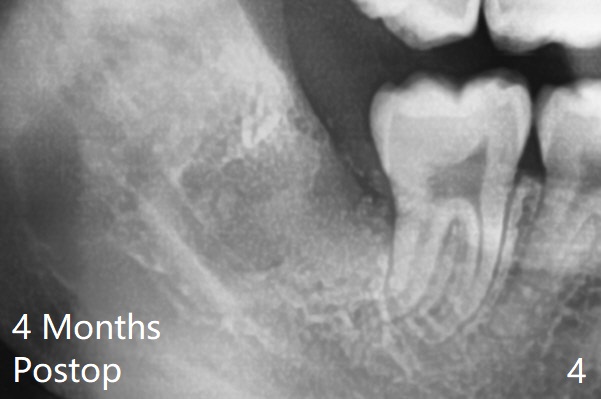

A 22-year-old man, asymptomatic, is going to have #1,16,17 and 32 extracted (Fig.1, fully bony impaction). For the large lower sockets (actually Buccal Impaction), collagen plug is placed in the inferior half, while Bone Cement (Bond Apatite from Augma (Fig.3 A)) and Osteogen plug (Fig.3 O) in the superior half at #32 and 17, respectively. Graft materials seem to spread into the lower haft of the sockets with apparent formation of new bone 4 months postop (Fig.4).